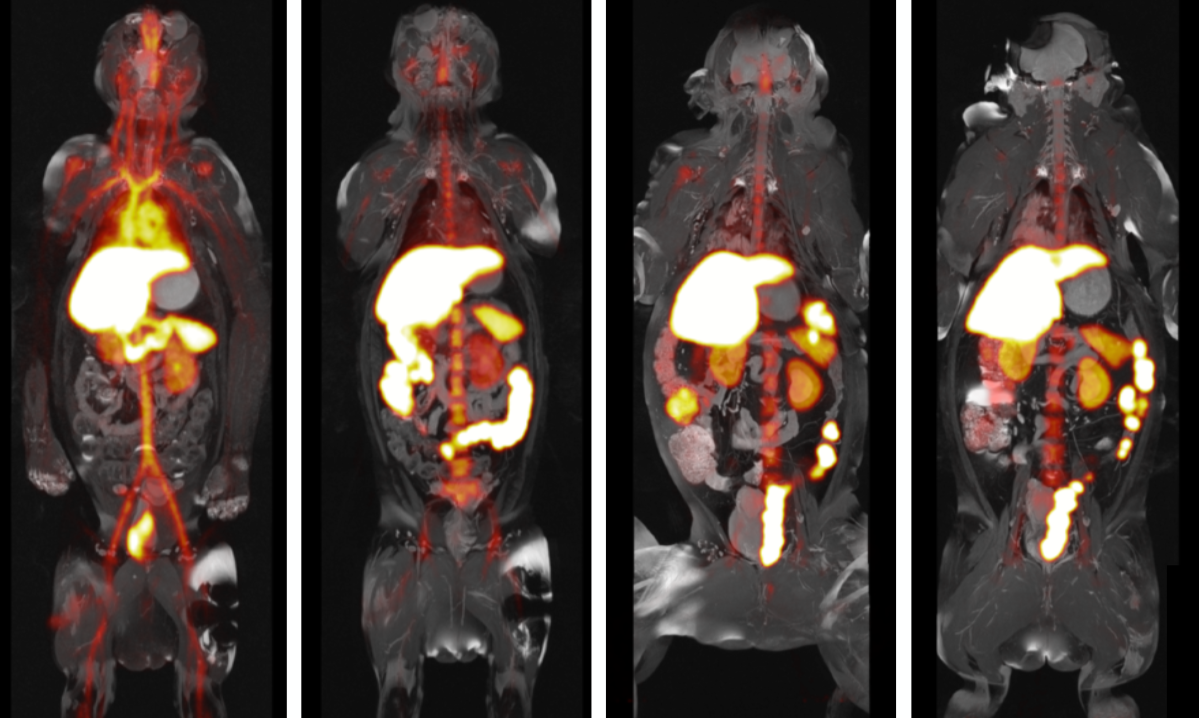

Although the mouse data were compelling, Prof. Mulder aspired to take the next step and bridge the gap between mice and humans. Around that time, Dr. Temel, from the University of Kentucky, approached us about safety studies in non-human primates. Dr. Calcagno, an imaging expert from Prof. Fayad’s group at Mount Sinai, and Dr. Binderup, an investigator from Copenhagen who has experience working with large animals, were involved in helping with PET/MRI biodistribution experiments in the same non-human primate model. This was a tremendous managerial challenge, ranging from animal husbandry, radiation safety, creating the radiolabeled nanoimmunotherapy, produced by Dr. Pérez-Medina, and the actual scan sessions. This resulted in unique PET/MRI data on nanoimmunotherapy biodistribution in non-human primates.

Movie 1. Whole-body three-dimensional rendered MR images acquired on a combined 3T PET/MRI system showing the anatomical structures of a non-human primate.